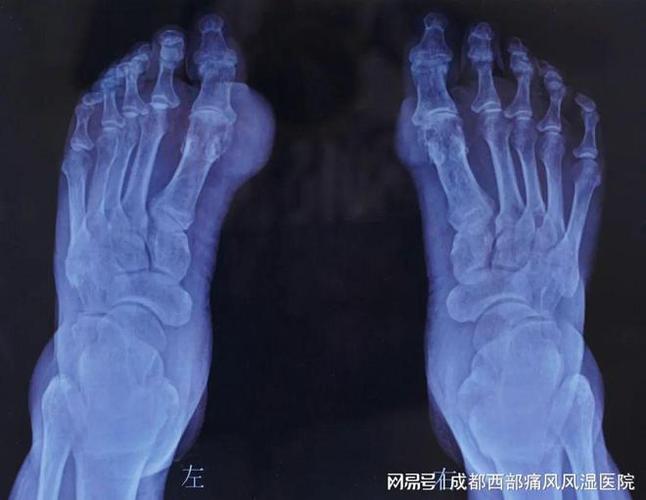

痛风脚关节黑色的临床发展阶段

根据病程进展,痛风关节的颜色变化可分为以下阶段:

| 阶段 | 临床表现 | 病理特征 |

|---|---|---|

| 急性期 | 关节红肿、皮温升高、疼痛剧烈,皮肤呈鲜红色或紫红色 | 血管扩张、炎性渗出、白细胞浸润 |

| 间歇期 | 红肿消退,但关节可能僵硬,皮肤颜色逐渐恢复正常或遗留轻微色素沉着 | 炎症缓解,但尿酸盐结晶持续存在 |

| 慢性期 | 关节肿大变形,皮肤增厚、变硬,出现暗褐色或黑色斑块 | 痛风石形成、纤维化、微循环障碍 |

| 溃疡期 | 痛风石破溃,流出白色牙膏样物质,创面周围皮肤发黑,伴异味或脓性分泌物 | 组织坏死、继发感染、含铁血黄素沉积 |